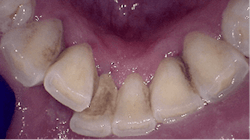

Air polishing accesses challenging areas more efficiently1,7 (figure 1) and reduces biofilm levels in periodontal pockets significantly more than hand-activated instrumentation.1,4,6 The PWR Pair offers the advantage of two powders:

- Sodium bicarbonate powder for the removal of heavier stain supragingivally Glycine powder for supra/subgingival access with a standard nozzle that reaches PD up to 4 mm and subgingival nozzle for PD up to 5 mm.1 A flexible narrow tip is attached to the subgingival nozzle to allow for subgingival access with minimal tissue distention (figure 2).1,3,6